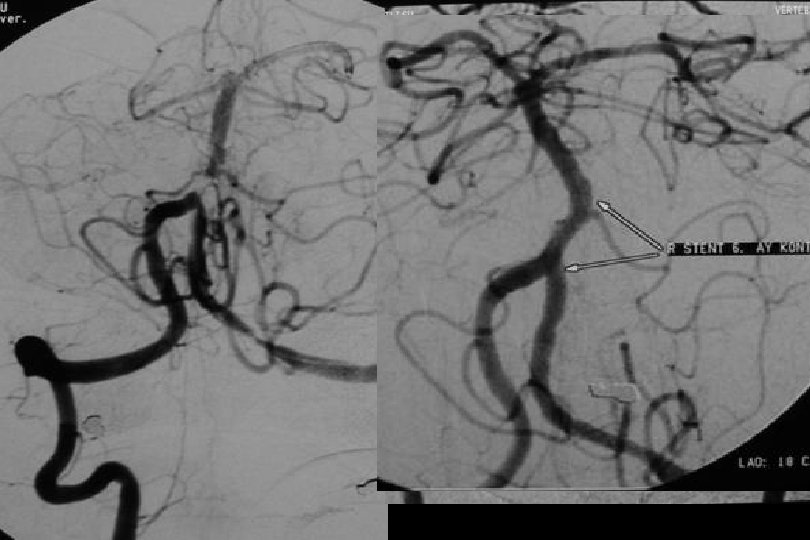

71 y kadın hasta En iyi medikal tedavi altında post fossa iskemik ataklara neden olan baziler stenoz

Sağ brakial yaklaşım ile Reflex /Navien servikal R- VA’e ve intrakraniyal segmente ilerletilmiştir.

• • • Distal Giriş Kateterleri Exchange in minumuma indirilmesi (primer gateway le bypass veya Reflex ve monorail balonla bypass pta balon Mikrokateterden bırakılan stent kullanılması

PTA sonrası

. . 6 mm Solitaire ile Stentleme sonrası

66 mm Solitaire ile post stent

Post stent